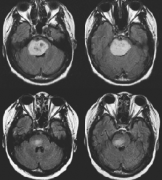

毛细胞星形细胞瘤约占全部儿童脑肿瘤的25%。在磁共振成像中,毛细胞星形细胞瘤通常是一种界限清楚的病变,通常具有囊性和结节状成分,可不均一地增...